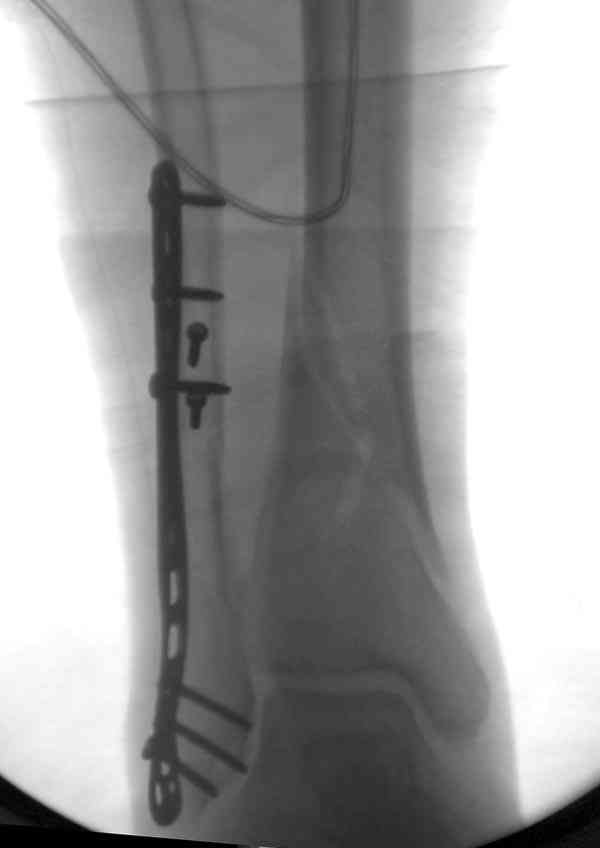

Для фиксации заднего края укладка больного в латеральном положении, конечность на подушке, доступ задне-латеральный, остеотомия заднего края. Опушенный на место фрагмент фиксируется butress пластиной.

Свежие случаи перкутанно, после репозиции временно спицами и через спицы 3.5 или 4.0 мм канюлированные шурупы. Направления шурупов не имеют значения, спереди назад или наоборот, главное, создание межфрагментарной компрессии.

Удлинение малоберцовой можно техникой вставления в зону остеотомии расширителя или инструментом из набора АО articulate tension device. Толкателем за счет проведенного в проксимальной части пластины

дополнительного шурупа. Пару снимков из этапов фиксации: мортизный снимок, техника фиксации

лодыжки, копии из книги